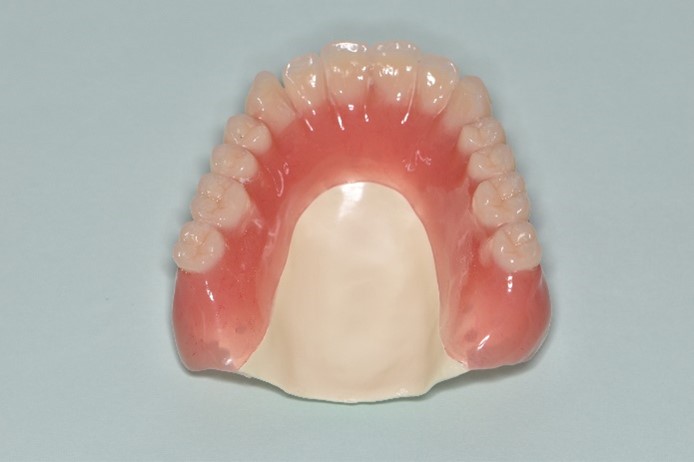

<症例>

78歳の男性。修理を繰り返した義歯で噛みにくくなったために総義歯治療を行った症例

治療後

治療内容:義歯の人工歯が摩耗していたうえに見た目にも支障があったため、旧義歯に代わって、BPS(生体機能的補綴システム)を利用して上下顎金属床義歯を製作しました。

治療期間・回数:約2か月間、5回

費用:800,000円(本症例は自由診療で診療を行いました)

リスク・副作用:経年的な顎骨の吸収に対する調整の必要性、義歯を装着している違和感など